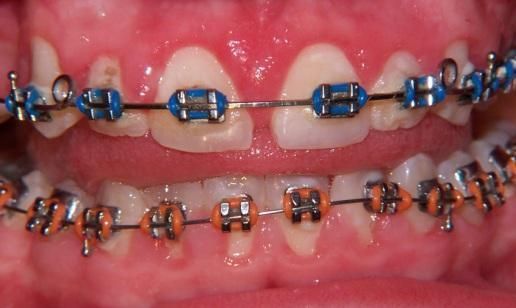

- Chirurgia mucogengivale

- Gengivectomia-gengivoplastica

- Parodontologia

Applicazioni Cliniche